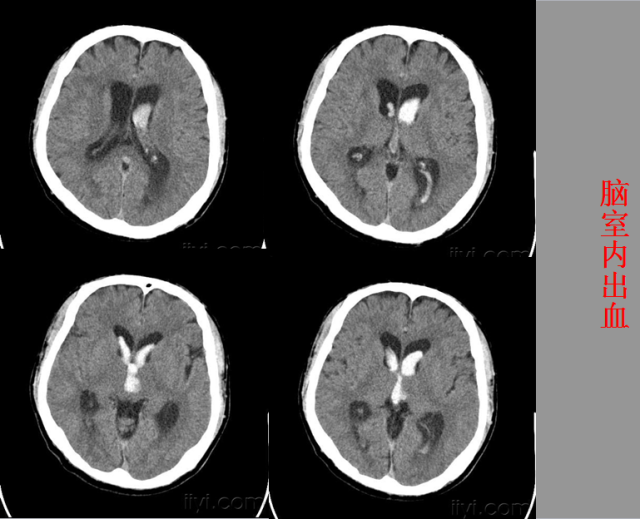

急性颅脑损伤篇

03